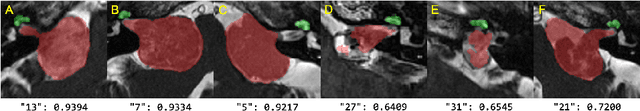

Abstract:Unsupervised cross-modality domain adaptation is a challenging task in medical image analysis, and it becomes more challenging when source and target domain data are collected from multiple institutions. In this paper, we present our solution to tackle the multi-institutional unsupervised domain adaptation for the crossMoDA 2023 challenge. First, we perform unpaired image translation to translate the source domain images to the target domain, where we design a dynamic network to generate synthetic target domain images with controllable, site-specific styles. Afterwards, we train a segmentation model using the synthetic images and further reduce the domain gap by self-training. Our solution achieved the 1st place during both the validation and testing phases of the challenge. The code repository is publicly available at https://github.com/MedICL-VU/crossmoda2023.

Abstract:Automatic segmentation of vestibular schwannoma (VS) and the cochlea from magnetic resonance imaging (MRI) can facilitate VS treatment planning. Unsupervised segmentation methods have shown promising results without requiring the time-consuming and laborious manual labeling process. In this paper, we present an approach for VS and cochlea segmentation in an unsupervised domain adaptation setting. Specifically, we first develop a cross-site cross-modality unpaired image translation strategy to enrich the diversity of the synthesized data. Then, we devise a rule-based offline augmentation technique to further minimize the domain gap. Lastly, we adopt a self-configuring segmentation framework empowered by self-training to obtain the final results. On the CrossMoDA 2022 validation leaderboard, our method has achieved competitive VS and cochlea segmentation performance with mean dice scores of 0.8178 $\pm$ 0.0803 and 0.8433 $\pm$ 0.0293, respectively.

Abstract:The cross-Modality Domain Adaptation (crossMoDA) challenge series, initiated in 2021 in conjunction with the International Conference on Medical Image Computing and Computer Assisted Intervention (MICCAI), focuses on unsupervised cross-modality segmentation, learning from contrast-enhanced T1 (ceT1) and transferring to T2 MRI. The task is an extreme example of domain shift chosen to serve as a meaningful and illustrative benchmark. From a clinical application perspective, it aims to automate Vestibular Schwannoma (VS) and cochlea segmentation on T2 scans for more cost-effective VS management. Over time, the challenge objectives have evolved to enhance its clinical relevance. The challenge evolved from using single-institutional data and basic segmentation in 2021 to incorporating multi-institutional data and Koos grading in 2022, and by 2023, it included heterogeneous routine data and sub-segmentation of intra- and extra-meatal tumour components. In this work, we report the findings of the 2022 and 2023 editions and perform a retrospective analysis of the challenge progression over the years. The observations from the successive challenge contributions indicate that the number of outliers decreases with an expanding dataset. This is notable since the diversity of scanning protocols of the datasets concurrently increased. The winning approach of the 2023 edition reduced the number of outliers on the 2021 and 2022 testing data, demonstrating how increased data heterogeneity can enhance segmentation performance even on homogeneous data. However, the cochlea Dice score declined in 2023, likely due to the added complexity from tumour sub-annotations affecting overall segmentation performance. While progress is still needed for clinically acceptable VS segmentation, the plateauing performance suggests that a more challenging cross-modal task may better serve future benchmarking.